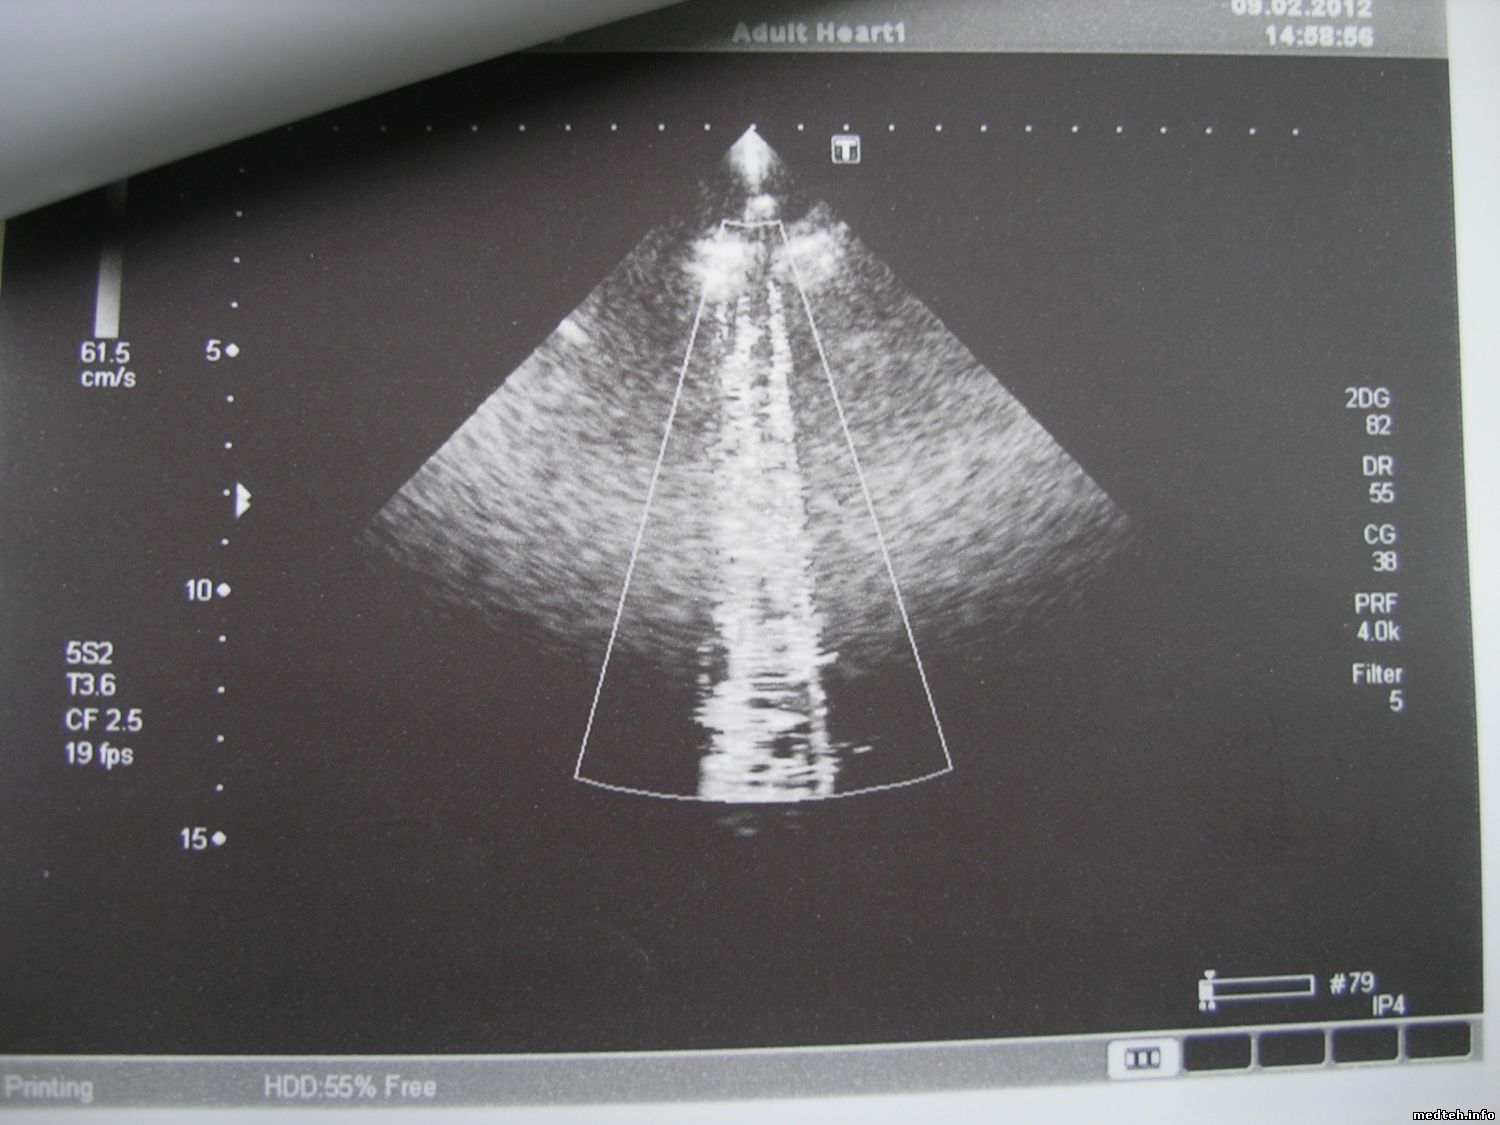

| Форум медтехников Медицинское оборудование (тех. разделы) УЗИ оборудование Помехи на УЗ-изображении... (БЕЗ ПРИВЯЗКИ К КАКОМУ_ЛИБО ПРОИЗВОДИТЕЛЮ) |

| Помехи на УЗ-изображении... | |||||||||